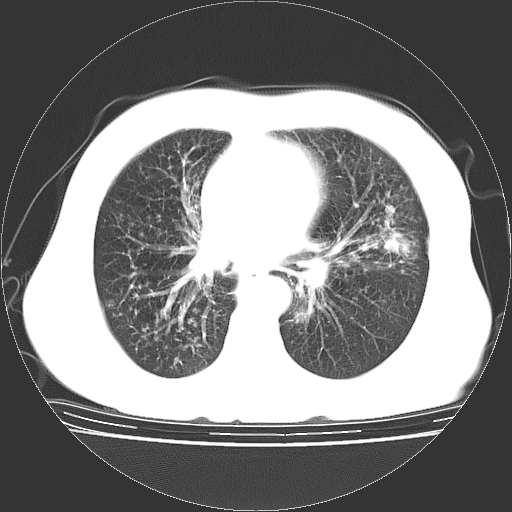

标题: CT23067:女,70岁,咳嗽、咳痰一个月,低热一周。 [打印本页]

女,70岁,咳嗽、咳痰一个月,低热一周。

1.左上肺结核,部分纤维化。右肺中下叶部分肺不张,内见液化、坏死及点状钙化,右中下叶支气管壁增厚、管腔狭窄,见多个点状钙化,结合临床考虑支气管内膜结核,建议痰检查抗酸杆菌并参考血沉。两肺多个小圆点状高密度灶,境界模糊,多考虑结核肺内播散。但本人年龄较大首先应支气管镜检以除外右肺癌。

3、两肺肺结核(右肺下叶背段及左肺)。